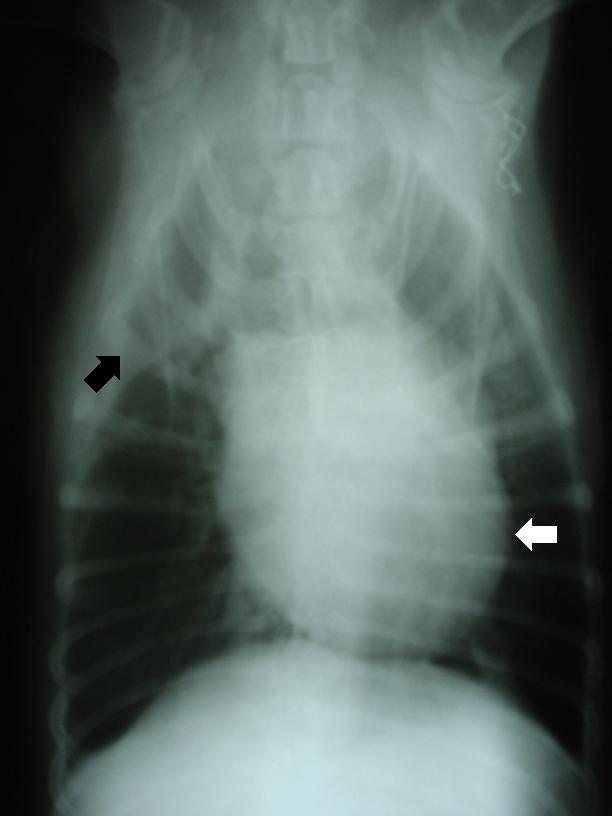

Nejprve rentgenologické vyšetření dutiny hrudní: Na kaudokraniální RTG projekci je vidět mírně zvětšená a diskrétně zakulacená srdeční silueta (bíla šipka) a výskyt menšího množství volné nitrohrudní (pleurální) tekutiny v pravé části hrudníku (černá šipka).

Hemoperikard-RTG-DV projekce